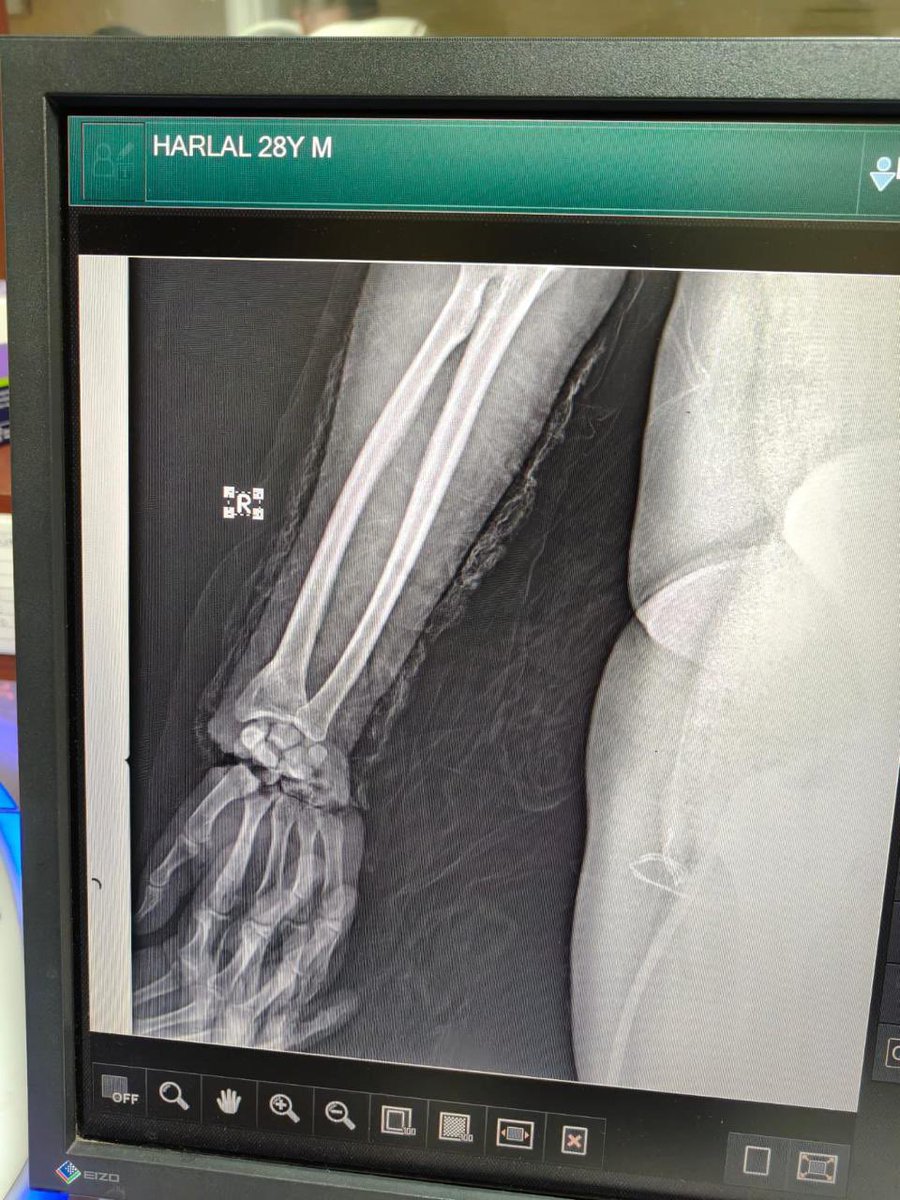

चिकित्सा में नई मिसाल! एम्स जोधपुर के चिकित्सकों की टीम ने 28 वर्षीय मरीज के दोनों कटे हुए हाथों का सफल प्रत्यारोपण किया। 10-12 घंटे की जटिल सर्जरी में प्लास्टिक सर्जरी, ट्रॉमा व ऑर्थोपेडिक्स विशेषज्ञों ने जीवन में नई उम्मीद जगाई। #AIIMSJodhpur #MedicalExcellence @JPNadda…